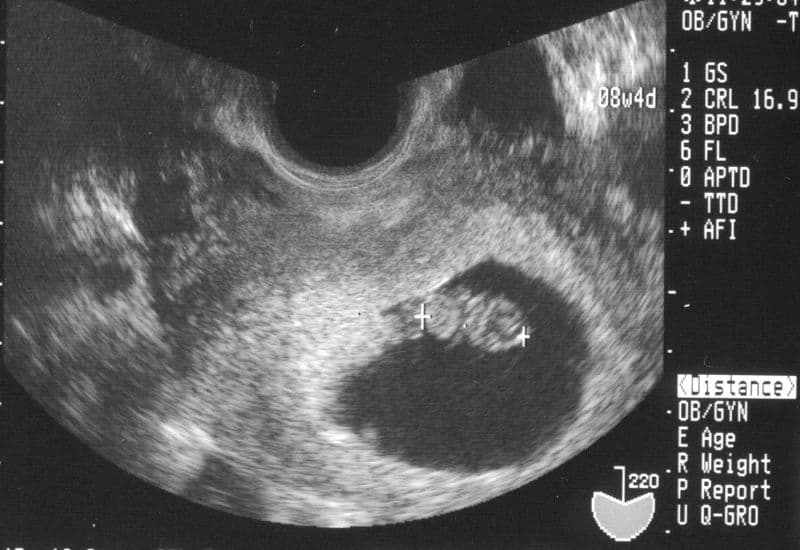

Về thắc mắc thai 8 tuần chiều dài đầu mông là bao nhiêu, con số tiêu chuẩn trung bình được các chuyên gia đưa ra là khoảng 16mm (tương đương 1.6cm). Để mẹ dễ hình dung, ở giai đoạn này em bé có kích thước chỉ bằng một quả mâm xôi và nặng khoảng 1 gram.

Kết quả đo chiều dài đầu mông thai 8 tuần sẽ được bác sĩ đối chiếu với bảng chỉ số thai nhi tiêu chuẩn để đưa ra kết luận về tình trạng của bé.